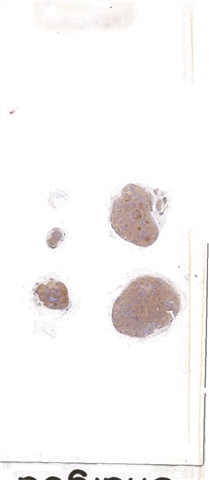

| 大体所见: | 颈部淋巴结4枚,直径0.2cm,0.4cm,0.8cm和1cm。 |